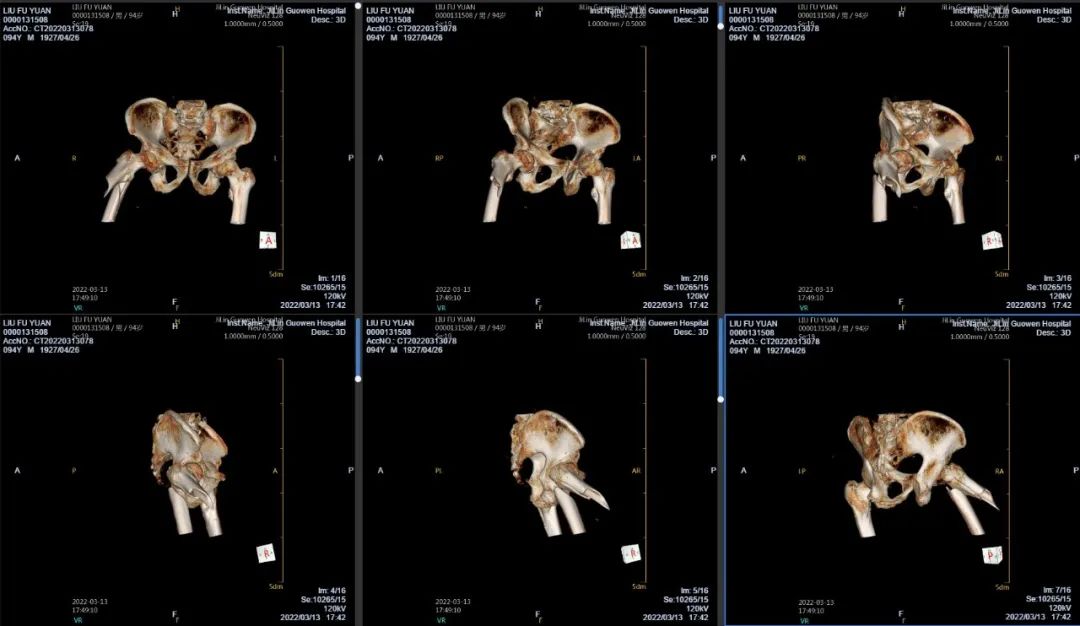

3月13日伴著急促的腳步聲、轆轆的車輪聲,夾雜著患者痛苦的呻吟聲,一位94歲的高齡老人被急診科醫(yī)護(hù)人員緊急送至骨科療區(qū)。這是怎么回事?呂國褔主任帶著值班醫(yī)生在做好防護(hù)措施后,第一時(shí)間來到患者病床前,經(jīng)急診科醫(yī)生診斷告知為 “股骨近端粉碎性骨折”,患者右大腿近端嚴(yán)重畸形,骨折端已經(jīng)刺穿前方肌肉直達(dá)皮下,局部皮膚高高隆起,局部皮膚有挫傷灶,呈青紫色,皮膚變薄,皮膚外可明顯觸及骨折斷端,右股骨X線片示:右股骨近端粉碎性骨折,斷端移位明顯,斷端銳利,近斷端位于前方皮膚下,局部皮膚隆起?;颊咛弁磩×?,痛苦難耐,測(cè)生命體征:血壓:220/110mmHg。

骨科醫(yī)生緊急會(huì)診評(píng)估,考慮到患者高齡,近百歲老人、同時(shí)患有高血壓3級(jí)(極高危),如急診手術(shù)、需要進(jìn)行全身麻醉,手術(shù)存在相當(dāng)大風(fēng)險(xiǎn);如不做手術(shù),骨折端已嵌于肌肉組織內(nèi)很難通過牽引復(fù)位,患者疼痛、肌肉組織收縮,很容易將皮膚刺破,變成開放性骨折,增加患者痛苦,影響預(yù)后。

面對(duì)如此高齡患者,為降低手術(shù)難度及麻醉風(fēng)險(xiǎn)。同時(shí)考慮到患者疼痛劇烈,無法配合腰麻,需要全麻。吉林國文醫(yī)院的專家團(tuán)隊(duì)們決定采取“有限切開,髓內(nèi)釘內(nèi)固定術(shù)”,該手術(shù)創(chuàng)傷小,風(fēng)險(xiǎn)低,術(shù)后有利于患者恢復(fù)。在麻醉科、心血管內(nèi)科團(tuán)隊(duì)的保駕下,于當(dāng)日夜間緊急為老人家實(shí)施手術(shù),手術(shù)歷時(shí)1個(gè)多小時(shí)。為能及時(shí)應(yīng)對(duì)患者出現(xiàn)術(shù)中血壓波動(dòng)大的風(fēng)險(xiǎn),麻醉科劉桂穎、程志超兩位主任及麻醉科值班醫(yī)生一直陪伴在老人身邊,監(jiān)護(hù)手術(shù)整個(gè)過程。